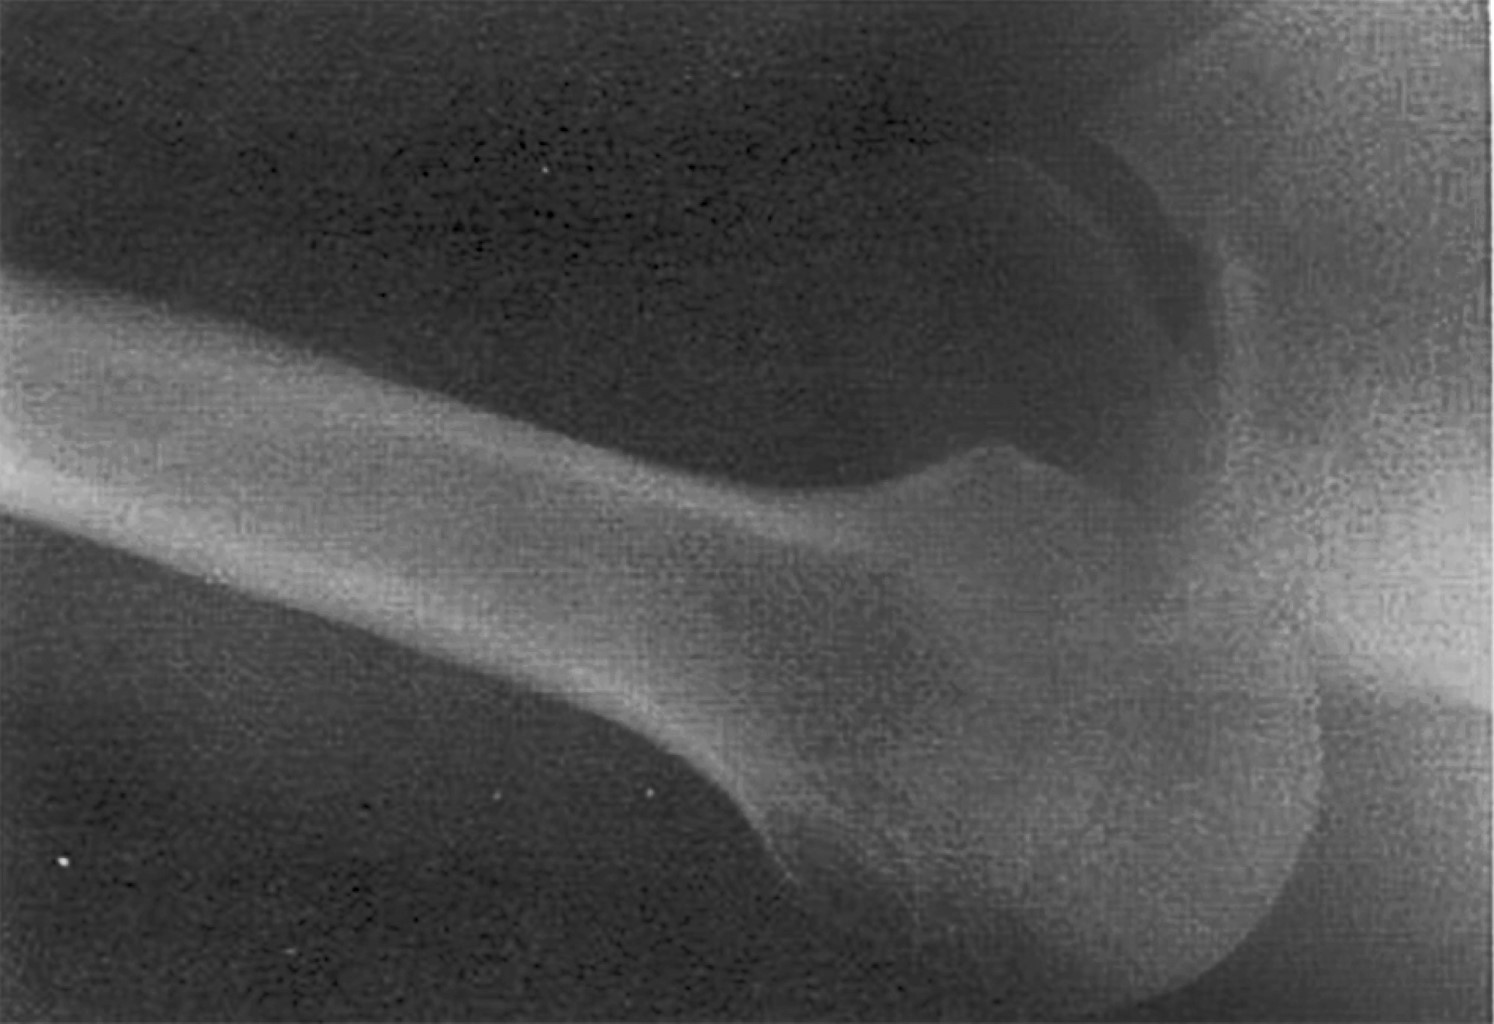

En una luxación glenohumeral anterior, la cabeza humeral se desplaza anterior e inferiormente, lo que da un aspecto de glena vacía en las radiografías AP de hombro; esto no sucede de igual manera en las luxaciones posteriores, donde la cabeza humeral se luxa hacia atrás sin desplazamiento inferior, resultando en la superposición de la cabeza humeral con la glena en la radiografía AP de hombro. La rotación interna del húmero da la apariencia redondeada de la cabeza humeral en la radiografía AP, conocido como "el signo de la bombilla". Otro signo que ayuda a diagnosticar esta lesión es el "Rim Sign", que se define como un espacio entre el borde medial de la cabeza humeral y el borde anterior glenoideo > 6 mm en las radiografías AP de hombro (Figura 3).9 En caso de sospecha de una luxación posterior de hombro y en ausencia de los signos previamente mencionados, es necesario tomar proyecciones radiográficas adicionales, como la escápula en Y o proyección axilar (Figura 4); esta última es la mejor para demostrar luxaciones posteriores, aunque puede ser difícil de obtener debido al intenso dolor del paciente.

Figura 3